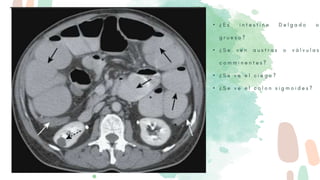

• ¿